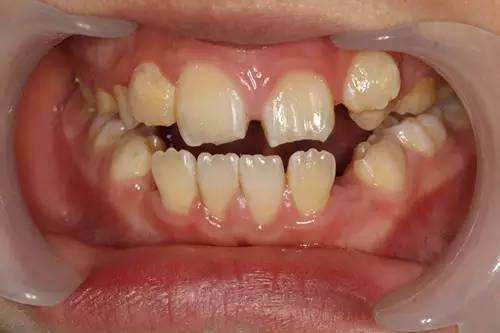

经过多次复诊,琪琪受伤的6颗牙都奇迹般的恢复了。

家长每次来都是千恩万谢的,任谁也不会相信,当时已经伤得“稀糟烂”,竟能恢复得完好如初。

看到孩子预后效果这么好,盛迪很是欣慰。

指着琪琪最近一次复查时留下的照片,盛迪骄傲地说:“看得出这和自然形态有什么区别吗?”